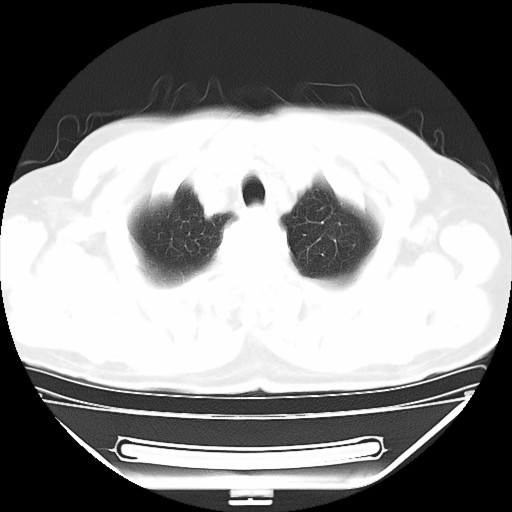

以下是引用hhcckk在2009-5-29 10:34:00的发言:[br]左下肺片絮状边缘模糊影,考虑感染,建议治疗后复查[br]